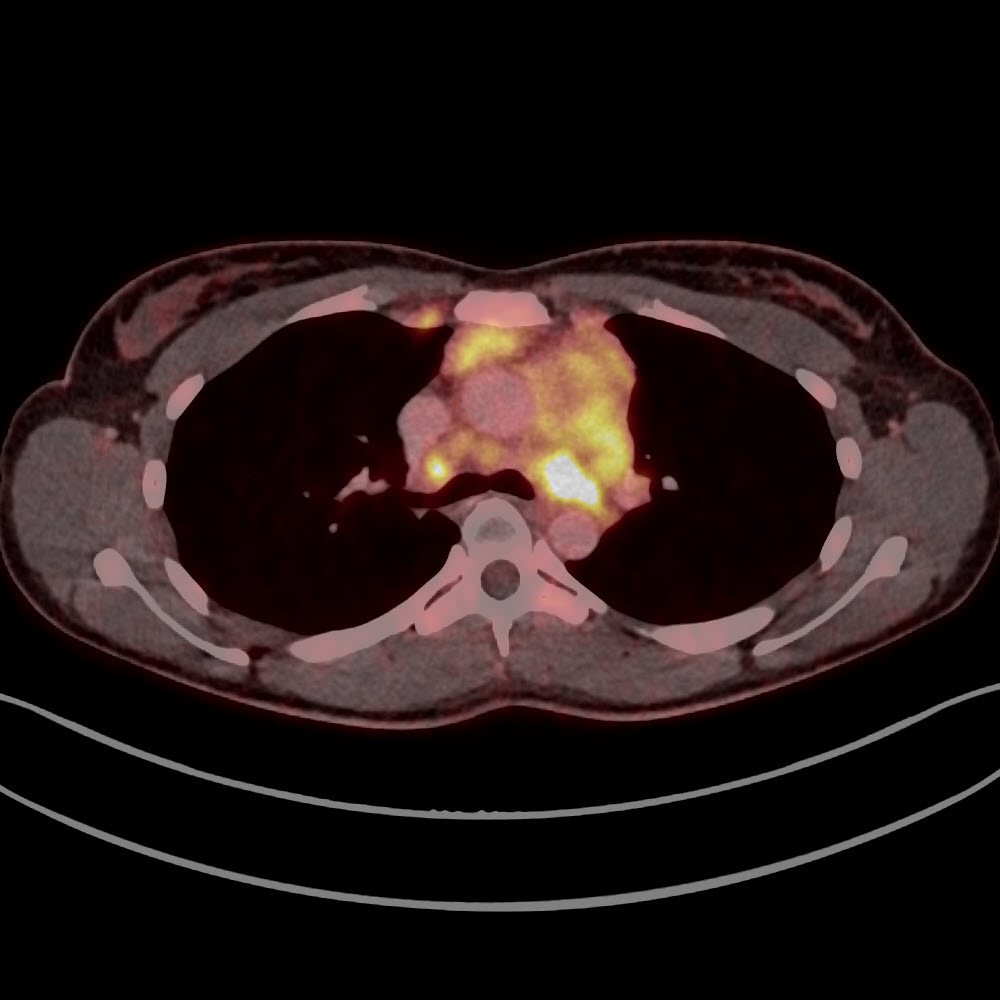

Lymphome im Mediastinum vor Therapie

Lymphome im Mediastinum nach Therapie